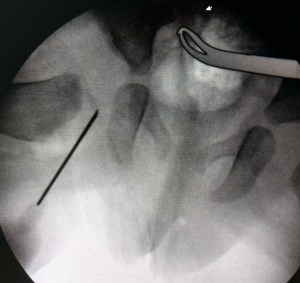

Arthrogram for DDH if a procedure of injecting a dye to visualise the head of the femur fully. The dye stains the cartilage which does not show up on the x-ray and helps visualisation.